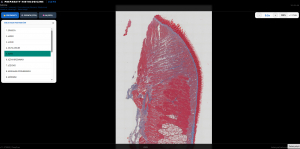

Z przyjemnością prezentujemy Przeglądarkę Preparatów Histologicznych AI, stworzoną we współpracy z Katedrą Histologii i Embriologii. Aplikacja oferuje dostęp do 20 starannie przygotowanych preparatów histologicznych oraz umożliwia ich pełny, intuicyjny podgląd w wysokiej jakości.

Nasze rozwiązanie to nie tylko przeglądarka — to zaawansowane narzędzie analityczne. Zintegrowane moduły analizy i przetwarzania obrazu pozwalają na automatyczne wykrywanie oraz liczenie struktur histologicznych, znacząco wspierając proces dydaktyczny i badawczy. Wykorzystujemy nowoczesne metody przetwarzania obrazu, bibliotekę OpenCV oraz dedykowane modele sieci neuronowych, które można elastycznie dopasować do konkretnych potrzeb.